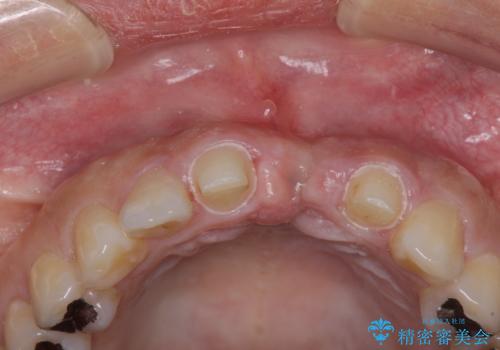

- 接着タイプの前歯のブリッジが不自然であるとのことで来院された患者様です。

欠損部の歯肉が窪んでいるため、歯肉移植により形態を改善し、オールセラミックブリッジにて補綴することとしました。

事前に装着されていた接着タイプのブリッジは、歯の切削量が少ない反面、接着界面から虫歯が進行しやすく、脱落リスクが高くなるというデメリットがあります。